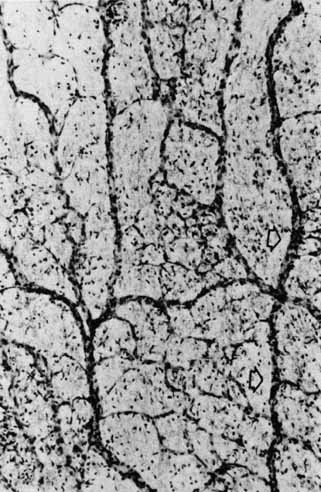

A cross section of a low-power histologic preparation of the retina in the region immediately peripheral to the area centralis shows it to have nine layers (Fig. 3). From internally (the side toward the vitreous), the layers are as follows:

Fig. 3 Light micrograph of human peripheral retina including portion of the choroid (Richardson's methylene blue/azure II stain mixture, 40× objective, Courtesy of Scheie Eye Institute). Inner limiting membrane (arrow): (1) nerve fiber layer, (2) ganglion cell layer, (3) inner plexiform layer, (4) inner nuclear layer, (5) outer plexiform layer, (6) nuclei of photoreceptors (outer nuclear layer), (7) rod and cone inner segments, (8) rod and cone outer segments, (9) pigment epithelium.